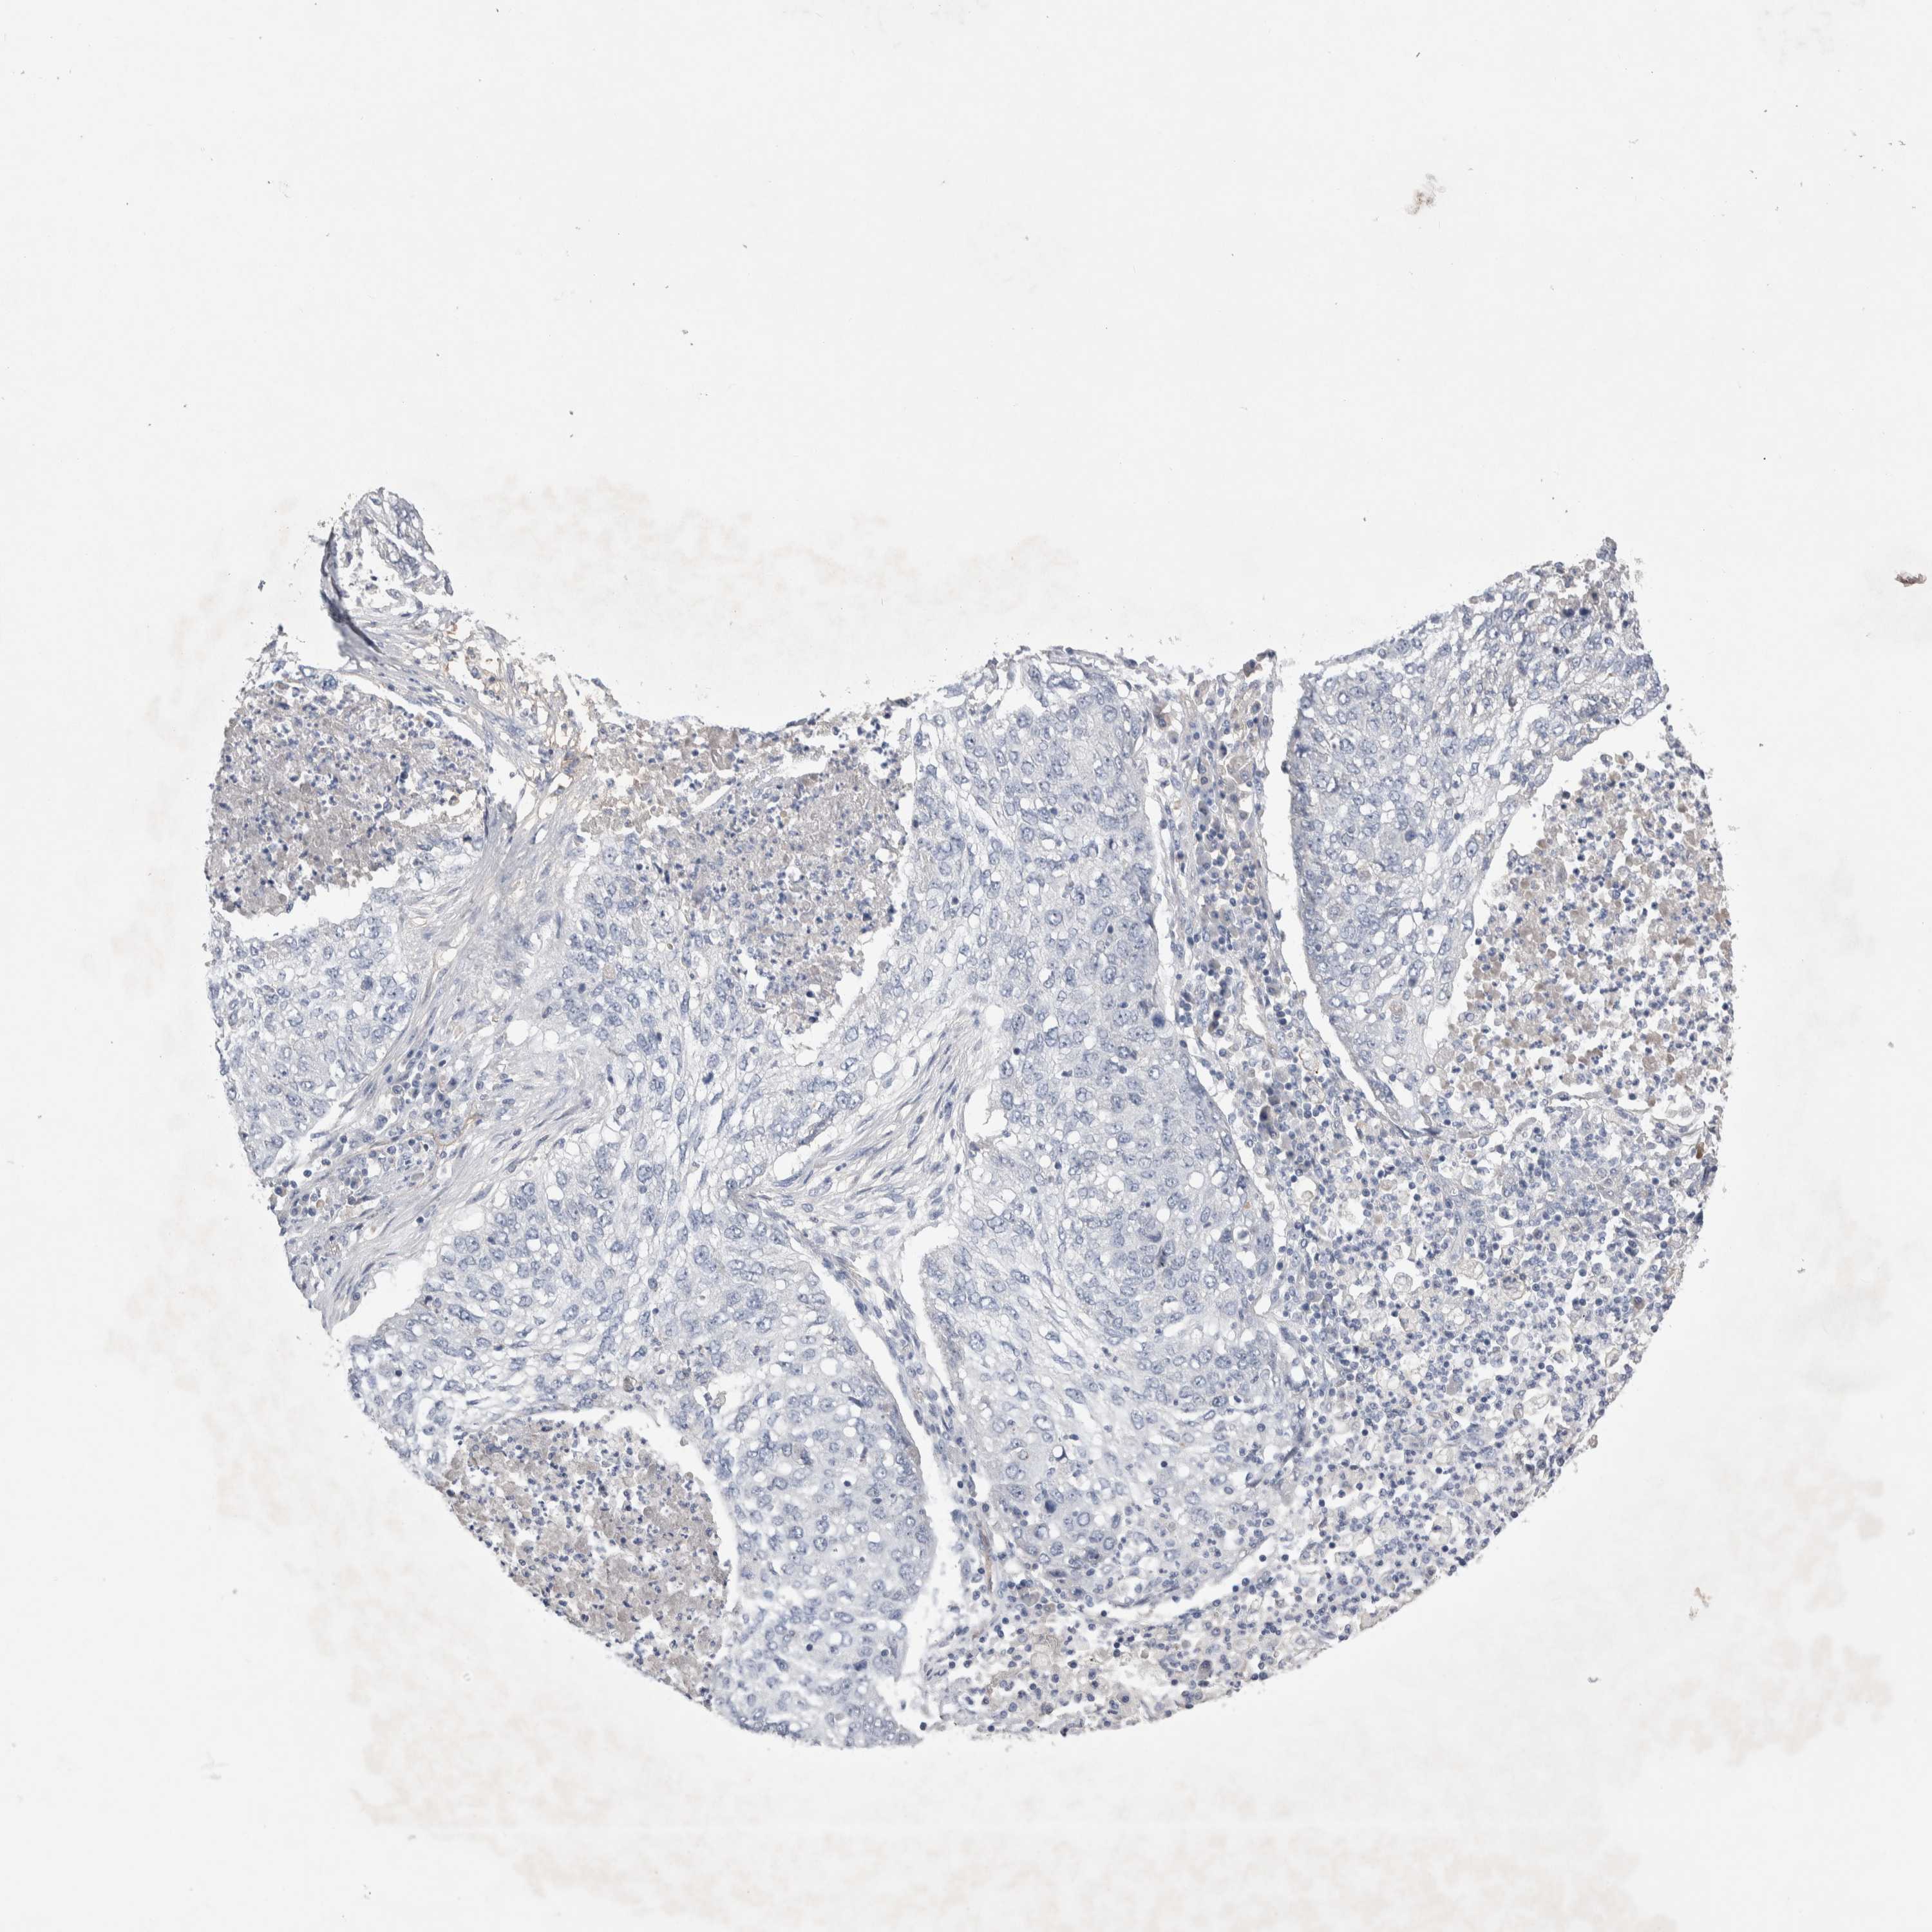

LUNG ADENOCARCINOMA (VALIDATION) - Interactive survival scatter ploti

The Survival Scatter plot shows the clinical status (i.e. dead or alive) for all individuals in the patient cohort, based on the same data that underlies the corresponding Kaplan-Meier plots. Patients that are alive at last time for follow-up are shown in blue and patients who have died during the study are shown in red.

The x-axis shows the expression levels (FPKM) of the investigated gene in the tumor tissue at the time of diagnosis. The y-axis shows the follow-up time after diagnosis (years). Both axes are complimented with kernel density curves demonstrating the data density over the axes. The top density plot shows the expression levels (FPKM) distribution among dead (red) and alive patients (blue). The right density plot shows the data density of the survived years of dead patients with high and low expression levels respectively, stratified using the cutoff indicated by the vertical dashed line through the Survival Scatter plot. This cutoff is automatically defined based on the FPKM cutoff that minimizes the p-score. The cutoff can be changed by dragging the vertical line or by entering a cutoff value in the square labeled "Current cut-off".

Under the Survival Scatter plot the p-score landscape (black curve; left axis) is shown together with dead median separation (red curve; right axis). Dead median separation is the difference in median mRNA expression between patients who have died with high and low expression, respectively. It is calculated as follows: median FPKM expression of dead patients with high expression - median FPKM expression of dead patients with low expression. This is intended to aid the user in visually exploring custom cutoffs and the associated p-scores and dead median separation.

Individual patient data is displayed and can be filtered by clicking on one or more of the category buttons on the top of the page. Categories describing expression level and patient information include: high, low, alive, dead, female, male and tumor stages. The scale of the x-axis can be toggled between linear and log-scale by clicking on the "x log" button. Mouse-over function shows TCGA ID, patient information and mRNA expression (FPKM) for each patient.

& Survival analysisi

Kaplan-Meier plots summarize results from analysis of correlation between mRNA expression level and patient survival. Patients were divided based on level of expression into one of the two groups "low" (under cut off) or "high" (over cut off). X-axis shows time for survival (years) and y-axis shows the probability of survival, where 1.0 corresponds to 100 percent.

CEP131 is not prognostic in Lung Adenocarcinoma (validation)

: 2.44

P scorei

N/A

Average pTPM 2.6

Number of samples 105